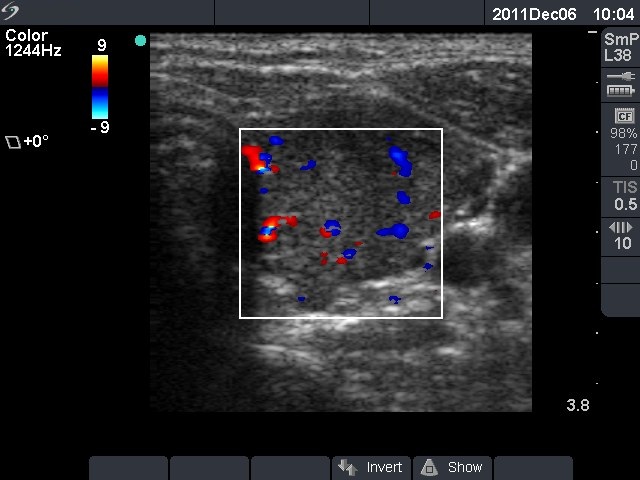

Second investigation - 3 months later (ultrasonographic picture 6)

Left lobe horizontal scan, color Doppler mode. The vascularization is a little bit increased.